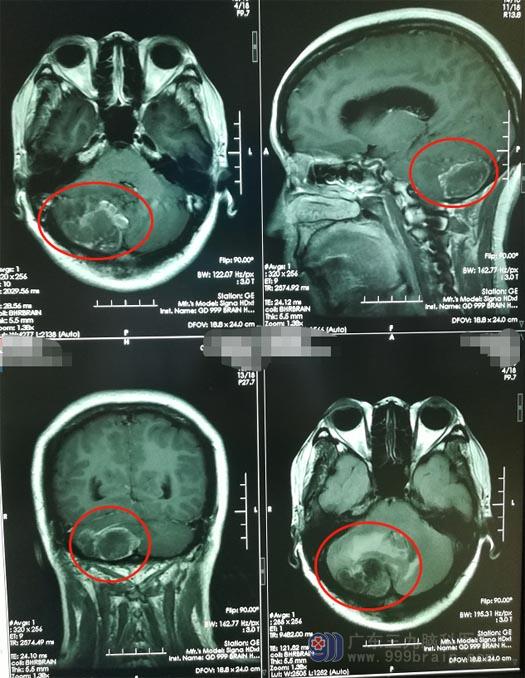

最近一段时间,蔡女士再次感到头痛,医生建议去专科医院进行进一步的治疗。广东三九脑科医院的头颅MRI检查显示:右侧小脑占位性病变,诊断为”右侧小脑半球转移瘤”。

蔡女士的肿瘤位于小脑,如果病灶继续增大,就会压迫脑干危及患者生命。神经外五科主管医生卢建侃与家属沟通病情后,患者同意手术治疗。

医院副院长、神经外五科主任鲁明带领团队为蔡女士施行“右侧小脑半球转移瘤切除术”;历时3个多小时,手术顺利结束,肿瘤被完整切除。术后,患者的生命体征稳定,神志清醒。在家人的悉心照料下,蔡女士恢复得很快。